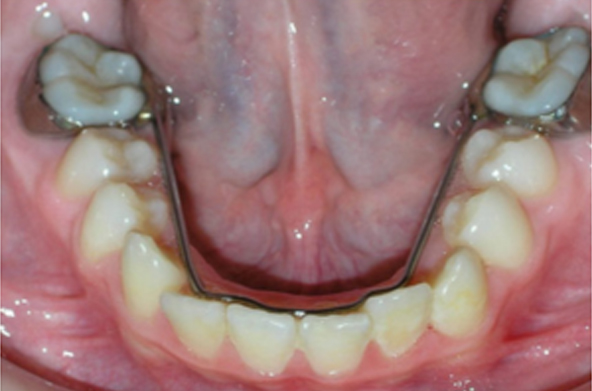

This space needs to be preserved in order for the permanent tooth to  come in straight. The dentist can save the space by putting in a space maintainer (spacer). When the permanent tooth is  ready to come in, the space maintainer is removed.

It can be either removable or in a child’s mouth. Space maintainers are an important treatment option for children because they can help reduce or even eliminate the need for future orthodontic work such as braces later on in your child’s life.